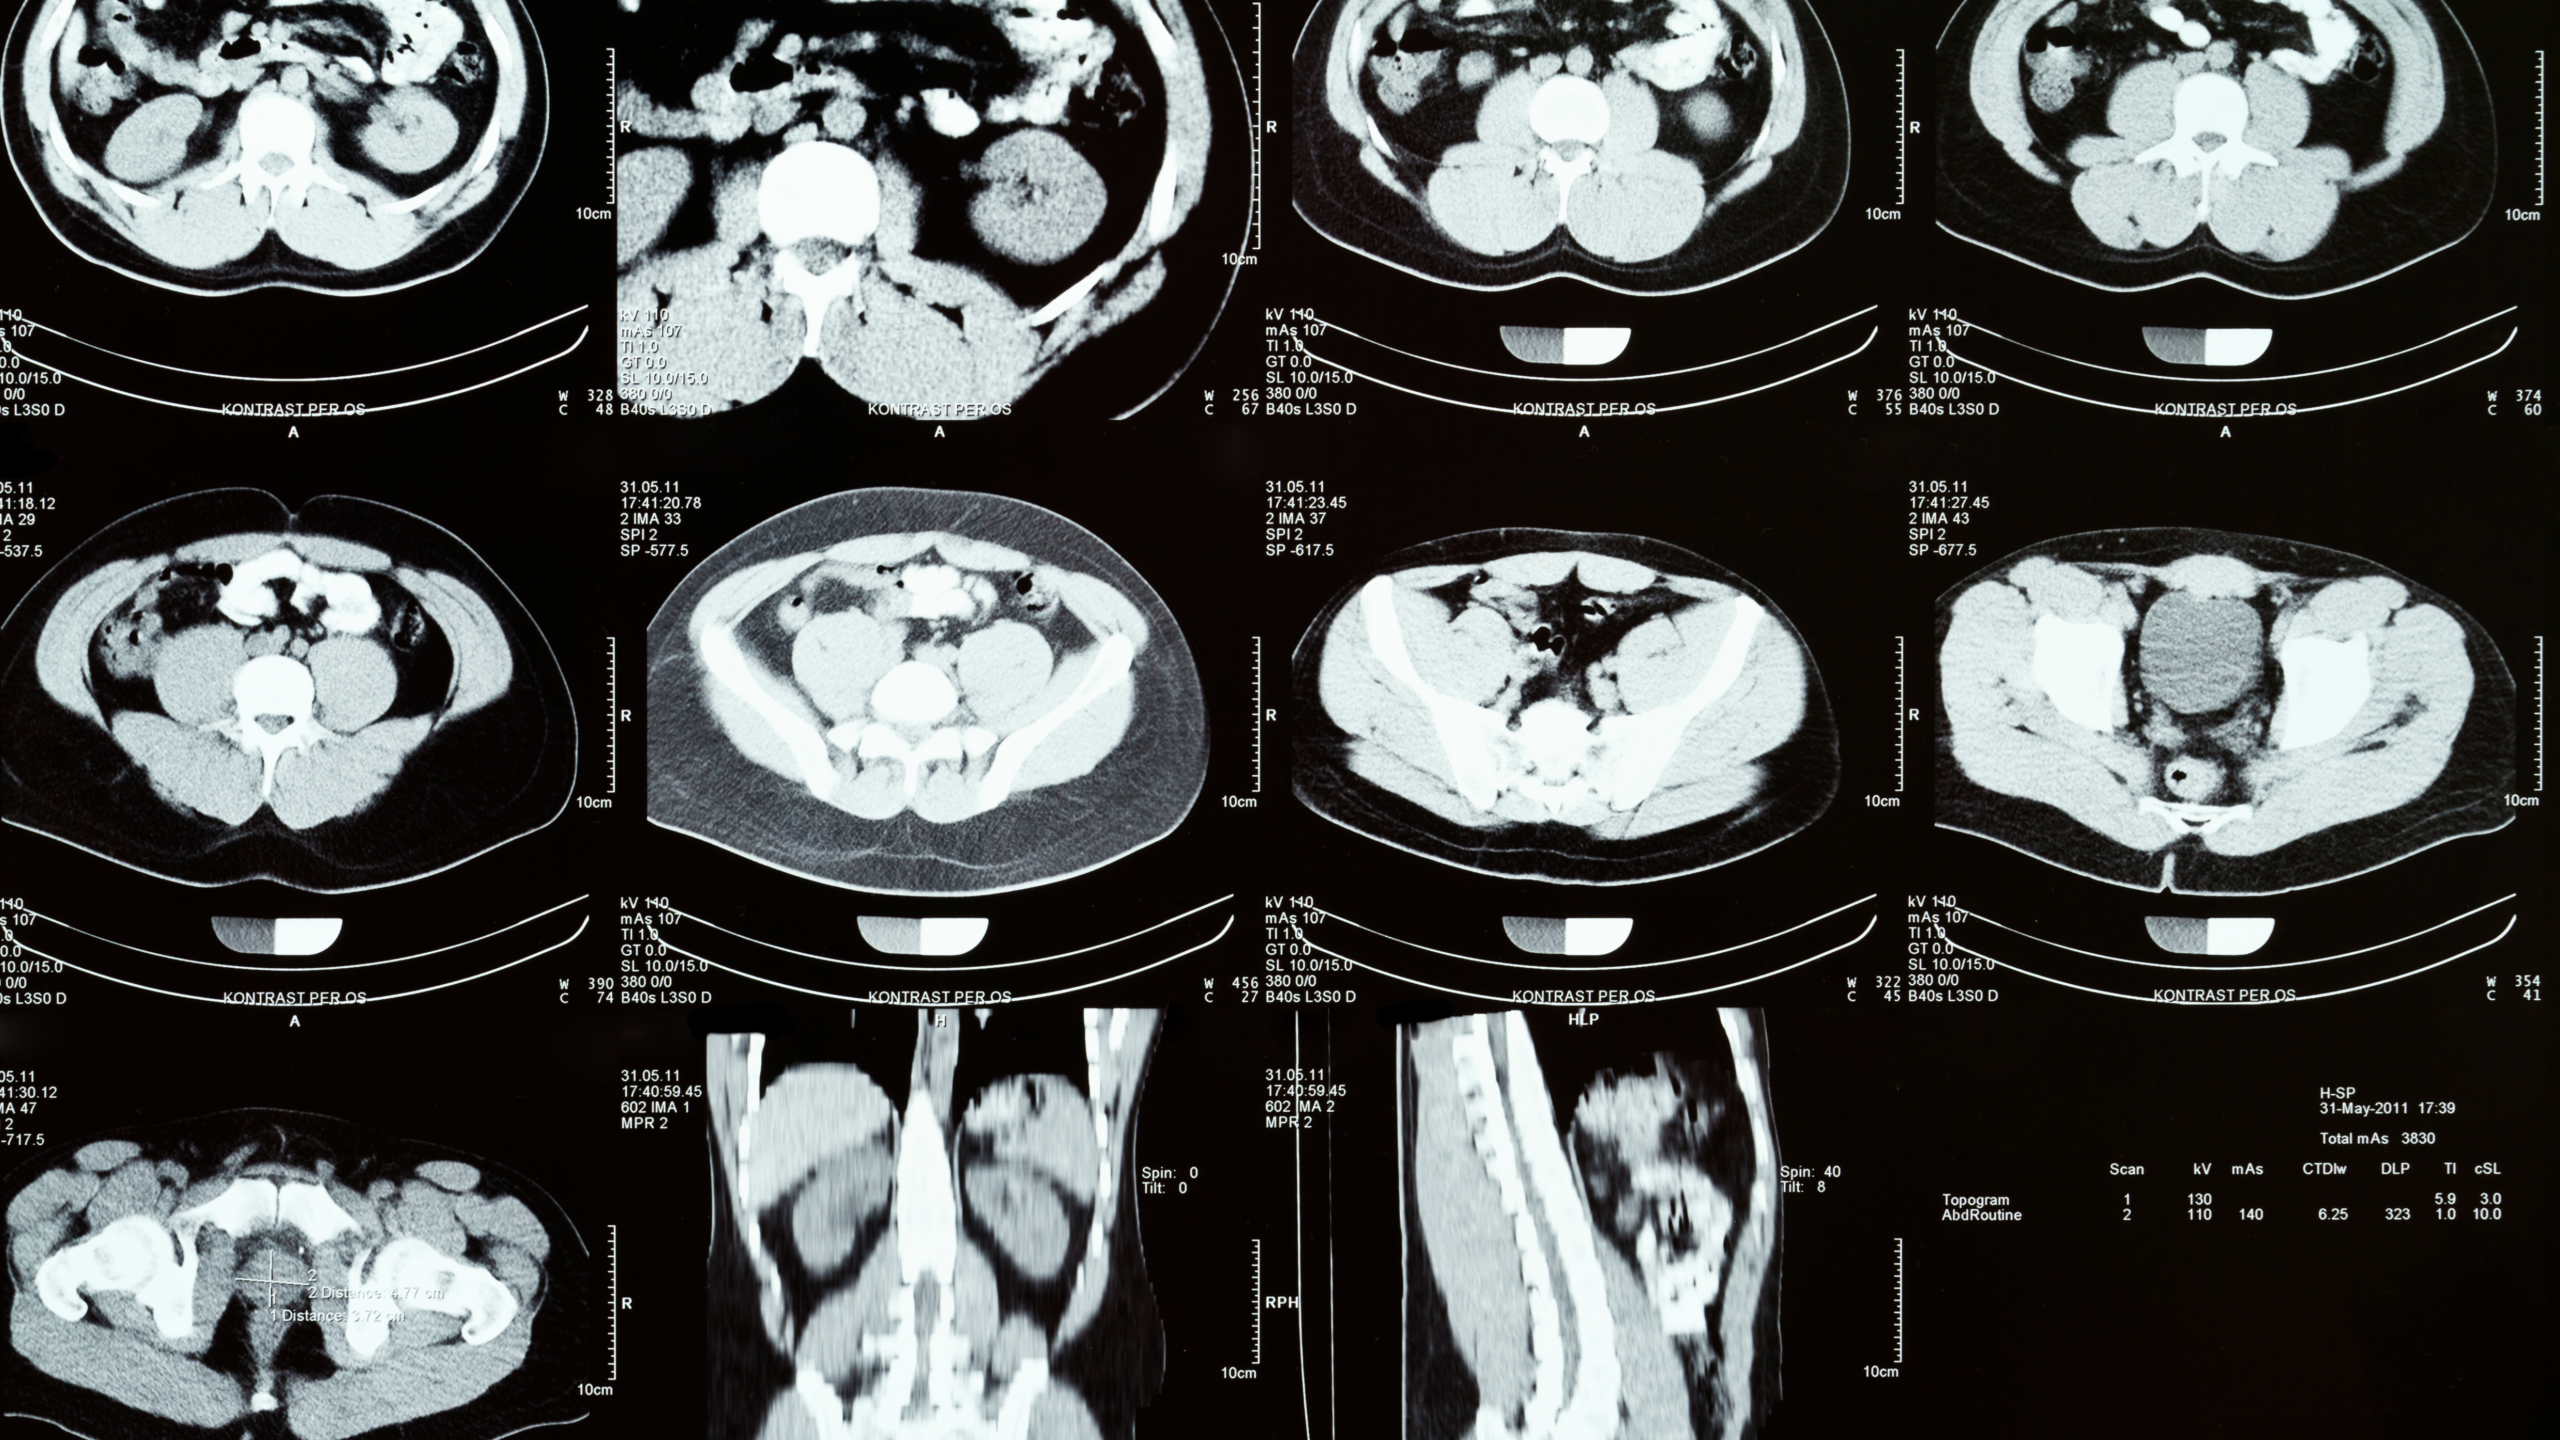

Tomografía (TAC)

La tomografía utiliza rayos X combinados con tecnología computarizada para generar imágenes detalladas del interior del cuerpo.